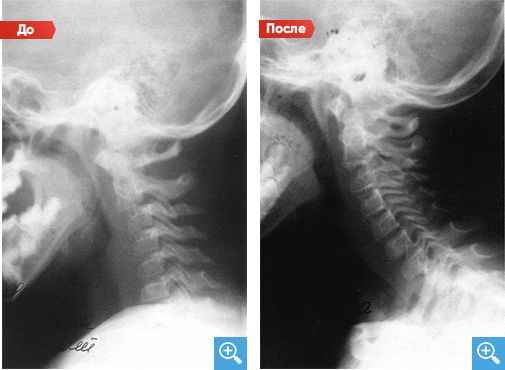

Сглаженный шейный лордоз

После проведения 4 недель Детензор-терапии по 45 минут 3 раза в день отмечается восстановление форм изгиба лордоза шейного отдела.